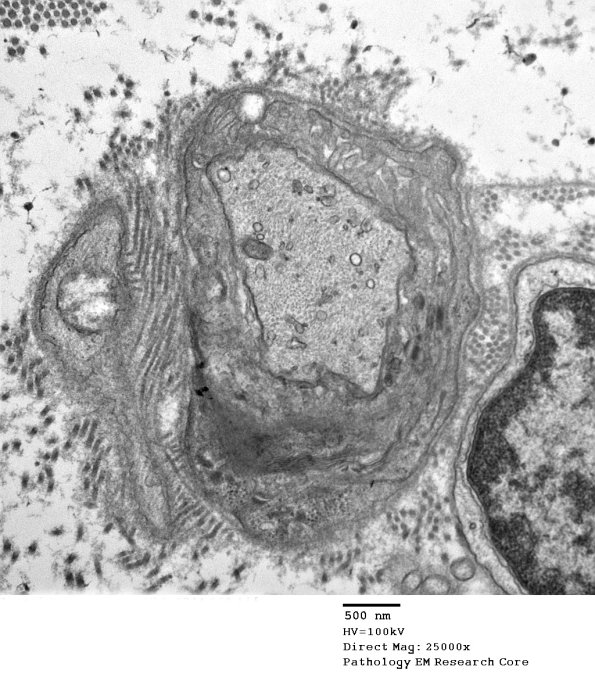

8A1-3 The node of Ranvier shows a similar increase in axonal contents and some variation in the appearance of the microvilli. (electron micrographs)